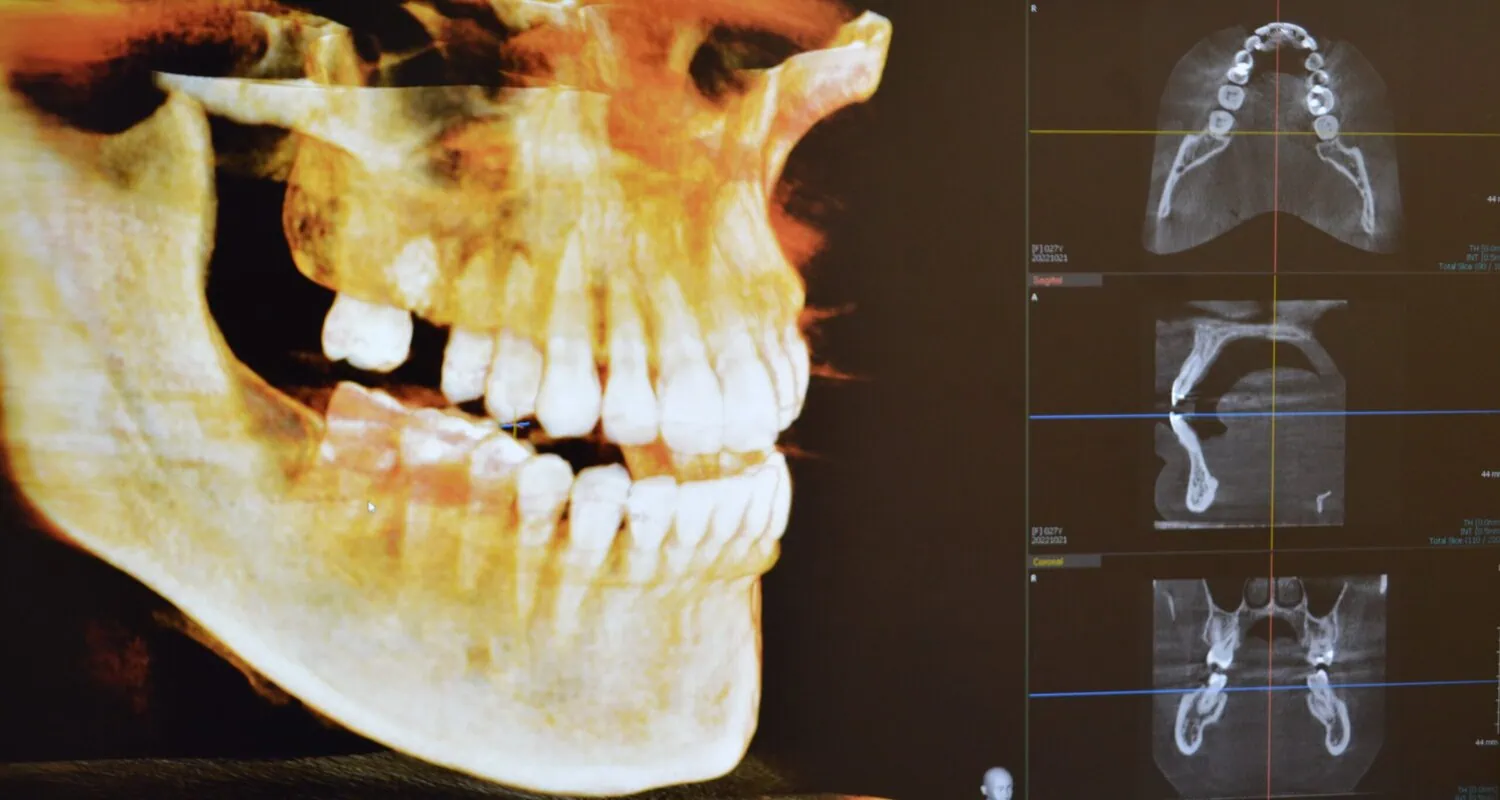

Our office is geared to provide patients with a modern and relaxing place to go to keep up with their dental needs. We use only the most cutting-edge technology in terms of dentistry and dental techniques so that you can feel comfortable bringing your entire family to us for care. We specialize in comprehensive dentistry and implantology and can accommodate both adults and children alike. New patients are welcome to join our growing family of satisfied patients.